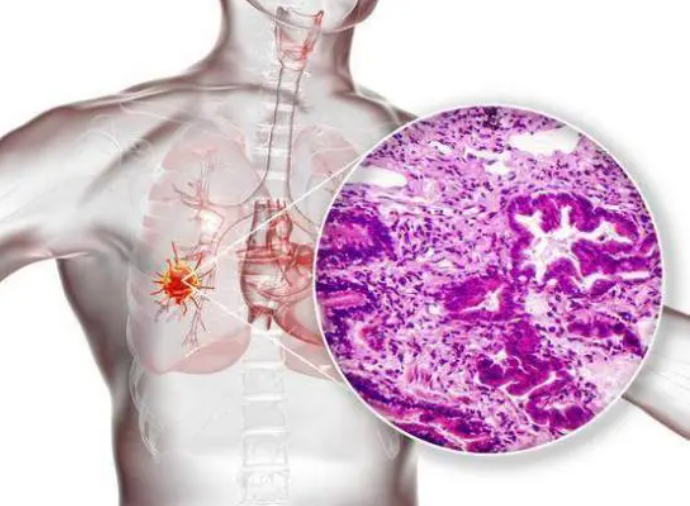

一、吸烟如何摧毁你的肺部?

吸烟就像在给肺部“埋地雷”,每一口烟雾都在一点点侵蚀它的健康,香烟里的7000多种化学物质中,有上百种是已知的致癌物,还有数千种对人体有害的化合物。

长期吸烟还会对肺组织造成结构性的破坏,正常的肺部应该是柔软有弹性的,就像气球一样能够自由膨胀和收缩。但香烟中的化学物质会让肺组织逐渐变硬,肺泡壁开始永久性地破裂,这种破坏无法修复,直接导致慢性阻塞性肺疾病(慢阻肺)的发生,让呼吸变得越来越困难。

健康的肺部是淡红色的,充满生机,而长期吸烟的肺部则会被杂质染成深黑色,甚至伴有硬化的斑块。这个黑色并不是简单的污渍,而是毒素的沉积,证明着肺部已经被烟雾侵蚀得无法自洁。

戒烟时间越长,身体的改善也越明显,一年后,心脏病的发病率会减少一半,这是因为血管逐渐恢复弹性,血栓风险降低。戒烟五年后,研究发现,肺癌风险显著下降,比持续吸烟者减少近40%,如果坚持十年以上不吸烟,某些疾病的发病率甚至可以接近非吸烟者的水平。